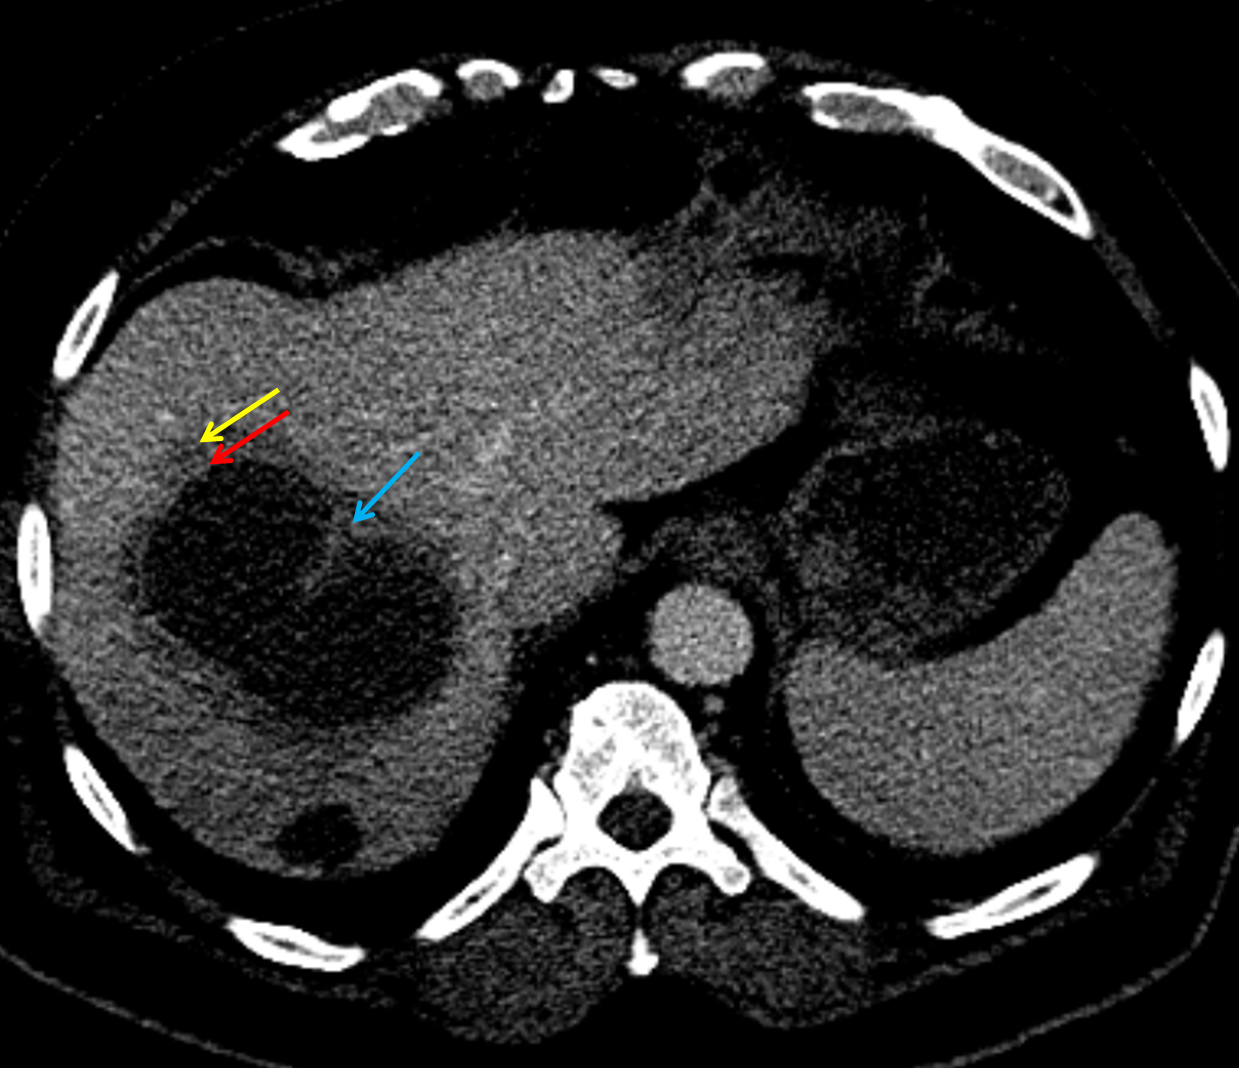

• Large fluid density structure in hepatic segments 7 and 8 measuring 10 x 7 x 7 cm with internal septation and circumferential ill-defined low density compatible with edema

• Peripherally enhancing subcapsular collections along the anterior margin of the left hepatic lobe measuring 3 x 1 cm and 2 x 1 cm

• The classic CT imaging appearance is a double target sign with internal low density surrounded by an internal enhancing rim (capsule) and a low density external rim (edema)

Hepatic abscess showing the double target sign with low density internally surrounded by a thin inner enhancing rim (red arrow) and ill-defined outer low density rim (yellow arrow). Blue arrow indicates an internal septation. Red arrows: additional smaller subcapsular abscesses. Red arrow: focal contained perforation associated with diverticulitis.